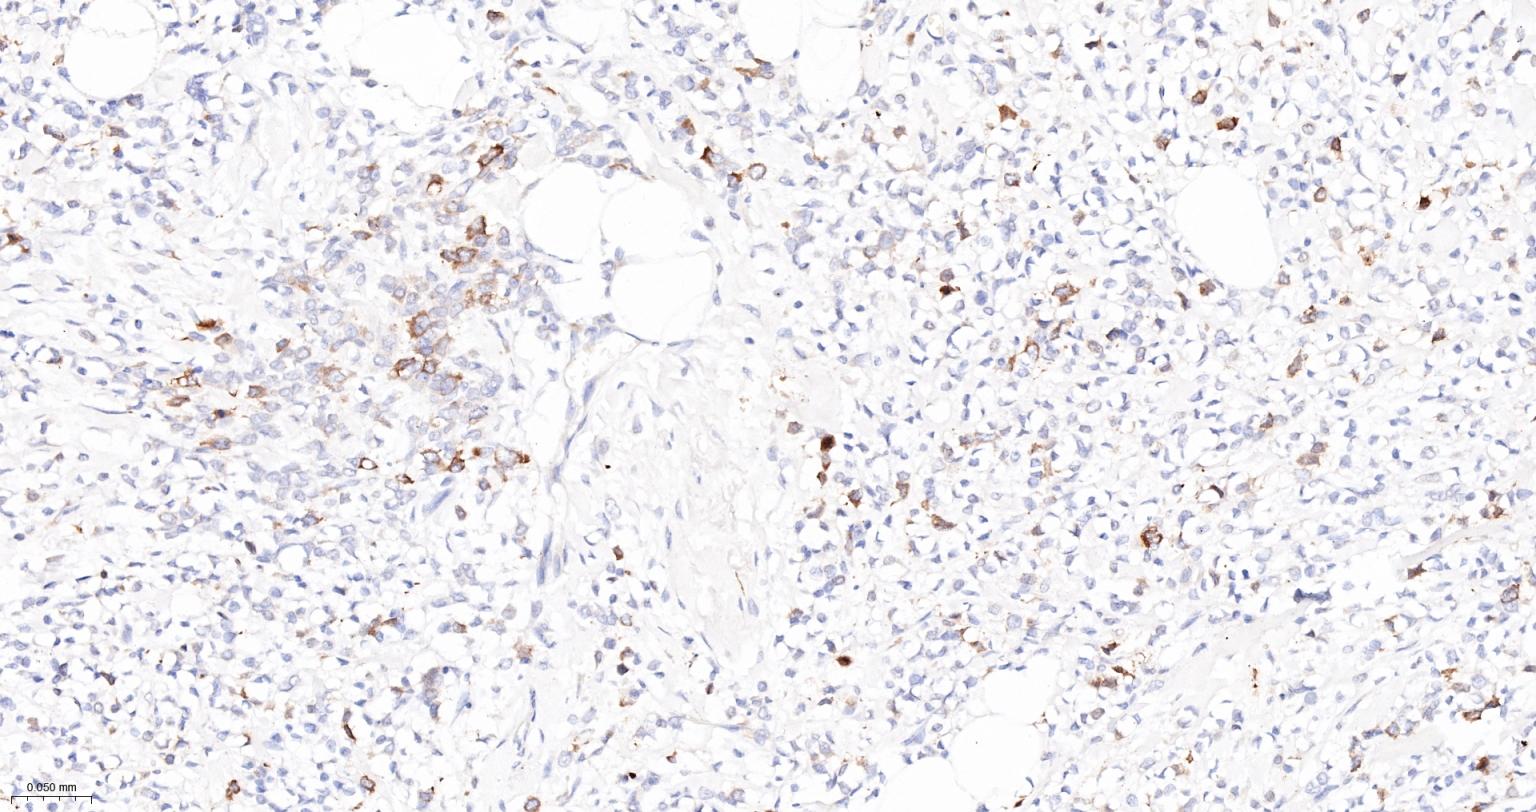

Paraformaldehyde-fixed, paraffin embedded Human Colon Cancer; Antigen retrieval by boiling in sodium citrate buffer (pH6.0) for 15 min; The section was incubated with TACC3 Monoclonal Antibody, Unconjugated (bsm-61119R) at 1:200 overnight at 4°C, followed by conjugation to the bs-0295G-HRP and DAB (C-0010) staining.